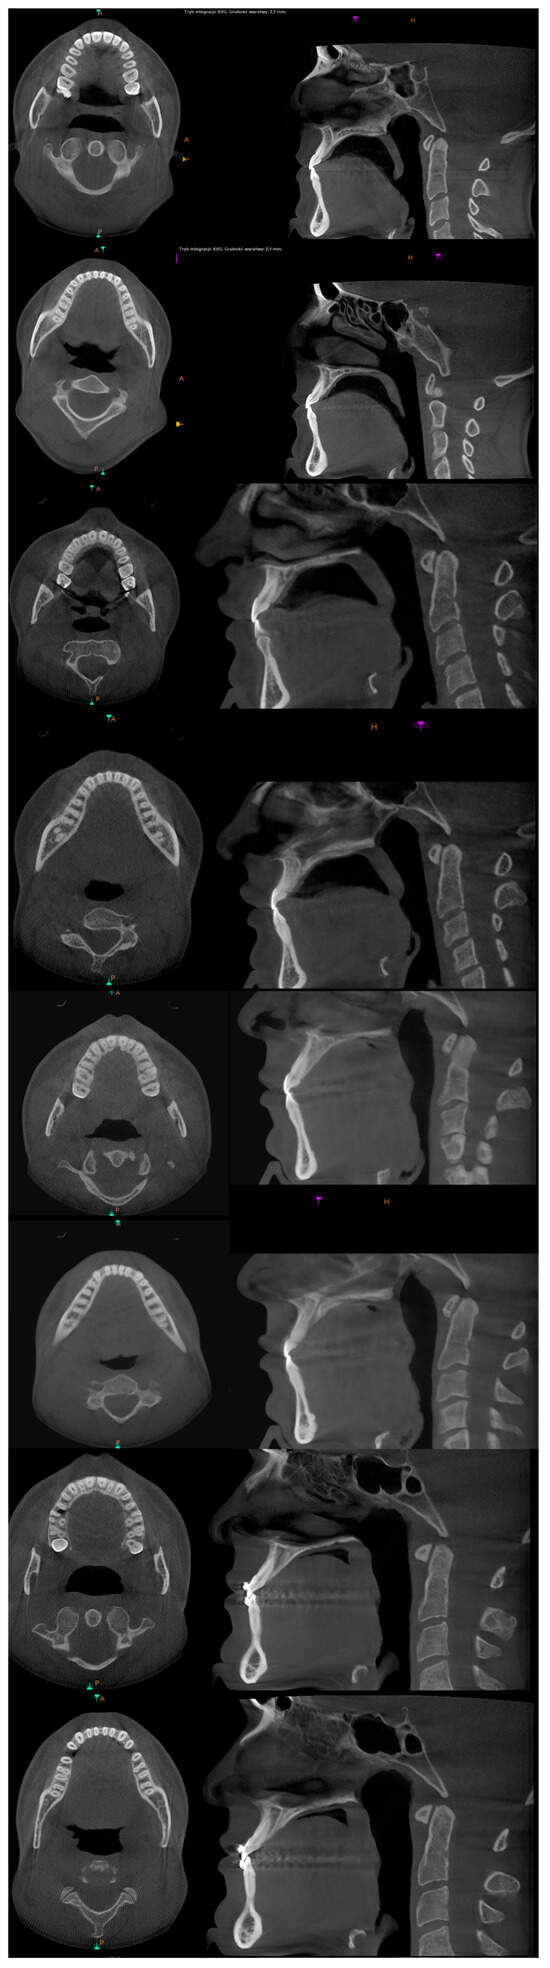

2. Materials and Methods

3. The Results of the Treatment